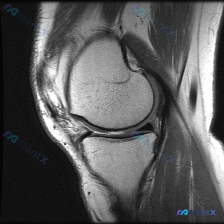

病例读片分享:膝关节MRI软骨异常的矛盾结果 刚整理了一份很有意思的读片病例,原提问说这张影像存在软骨异常,但我们完整分析完,结果和提问的判断矛盾,给大家分享一下整个过程。 影像基本信息 这是一张膝关节MRI冠状位影像,考虑是质子密度加权(PDWI)序列,这类序列分辨率高,非常适合观察膝关节的半月板...